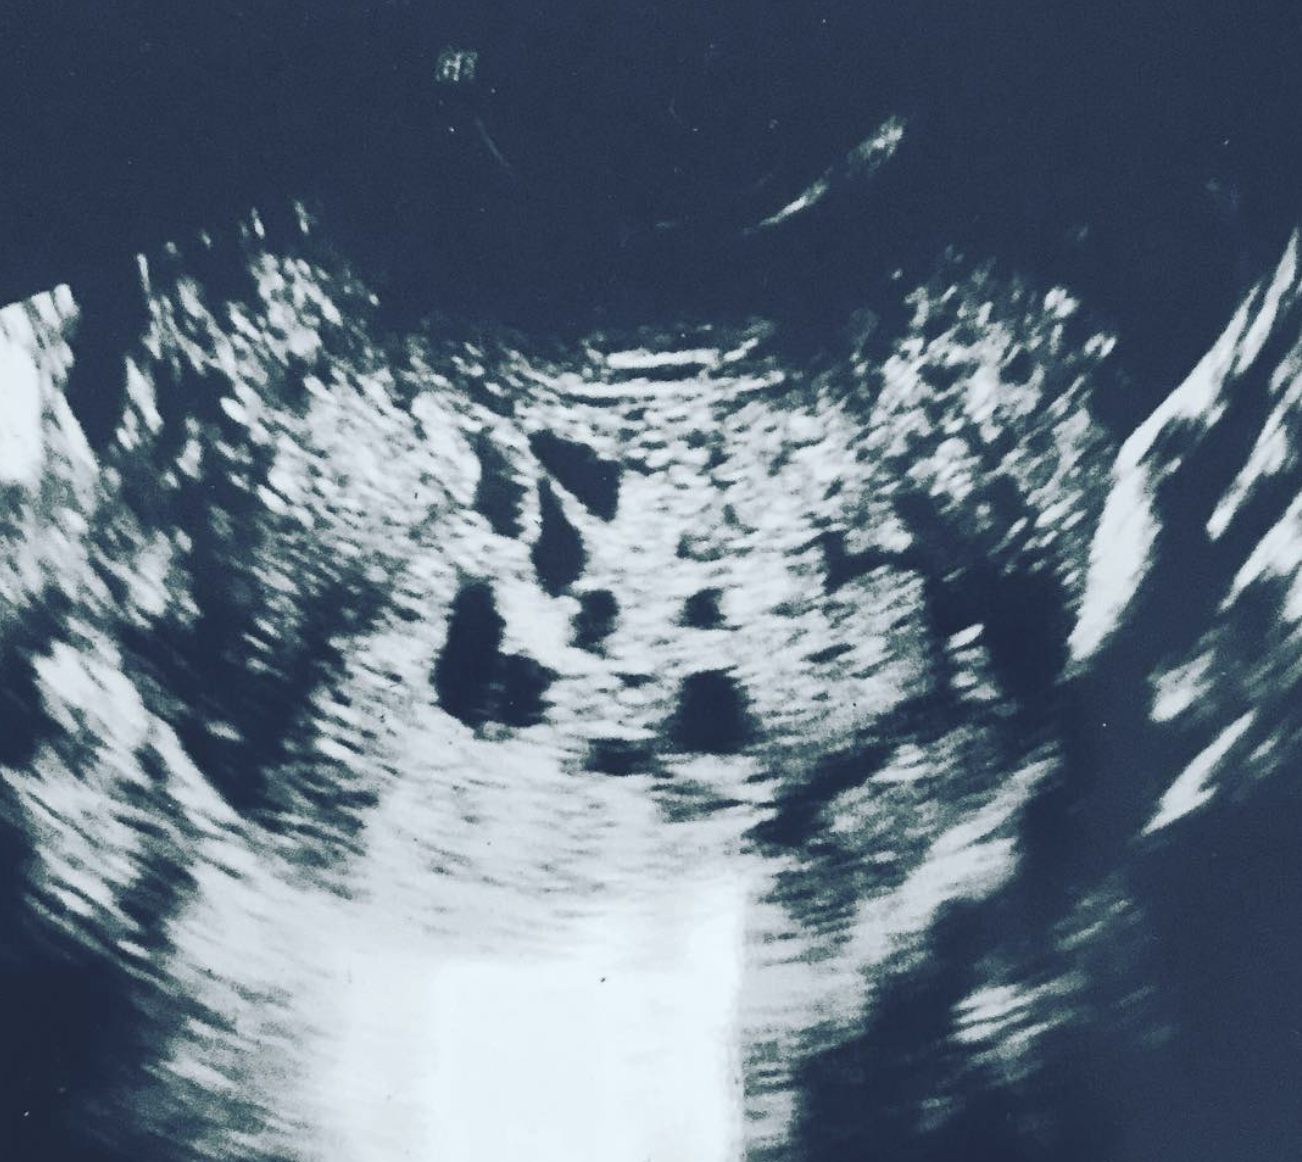

Después de la ecografía, los médicos informaron: no hay feto alguno en desarrollo en el abdomen, sino que se trata de un llamado «embarazo molar». En este estado patológico, el óvulo fertilizado no se desarrolla como se esperaba y, a veces, está completamente ausente.

Pronto al diagnóstico inicial se agregó la enfermedad trofoblástica. Según los médicos, en el útero de Lauren se desarrolló no un bebé, sino un tumor canceroso. La quimioterapia y la cirugía para extirpar el tejido infectado no detuvieron la terrible enfermedad, sino que solo ralentizó su desarrollo.